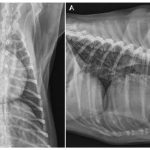

Understanding Dilated Cardiomyopathy in Dogs: Symptoms, Causes, and Treatment

Discover the signs, causes, and treatment options for Dilated Cardiomyopathy in dogs. Learn how to support your furry friend’s heart health effectively.